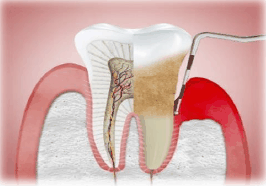

Segundo a Organização Mundial da Saúde (OMS), as doenças bucais são apontadas como um grande ponto de atenção para a saúde pública de muitos países. Estima-se que essas doenças afetem cerca de 3,5 bilhões de pessoas no mundo. Dentre os agravos bucais, as doenças periodontais representam grande parte dessa alta prevalência.

A doença periodontal é uma inflamação dos tecidos que suportam os dentes, ocasionada pelo acúmulo duradouro de quais bactérias?